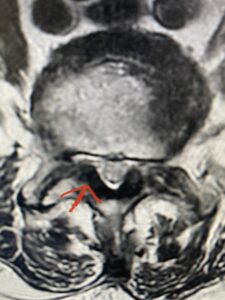

Fig 1: Sagittal T2-weighted lumbar MRI demonstrating grade 1-2 spondylolisthesis L4-5 with severe stenosis (red arrow)

Another patient is a 62 year-old female with progressive low back pain and right leg pain and numbness that radiates to the top of her foot. She tried physical therapy and epidural injections. MRI demonstrated severe L3-4 stenosis and a grade 1 spondylolisthesis (Fig 4). There was L5-S1 and L4-5 disc collapse with modic end-plate changes. Biomechanically because of the significant degeneration of these disc spaces which stiffened the L4-S1 segment more stress was placed on the L3-4 segment, resulting in significant premature degeneration and compensatory stenosis and segmental instability. The MRI also showed pathologically, because of the slip, the L3 inferior processes were more anteriorly oriented and hence contributing to the majority of the lumbar canal compromise. Note the more sagittally-oriented facets in this case compared to the prior case (Fig 5). The patient underwent a decompressive laminectomy with attention of removing the inferior processes of L3 to fully decompress the canal. We also performed an L3-4 fusion with instrumentation (Fig 6). The patient had an uneventful postoperative course with improvement of leg pain. Of note with relief of the disabling leg pain patients are generally very happy. Patients can often manage their low back pain; it is the leg pain that they just can’t tolerate.

Fig 4: Sagittal T2-weighted lumbar MRI demonstrating L3-4 grade 1 spondylolisthesis with severe stenosis (blue arrow)